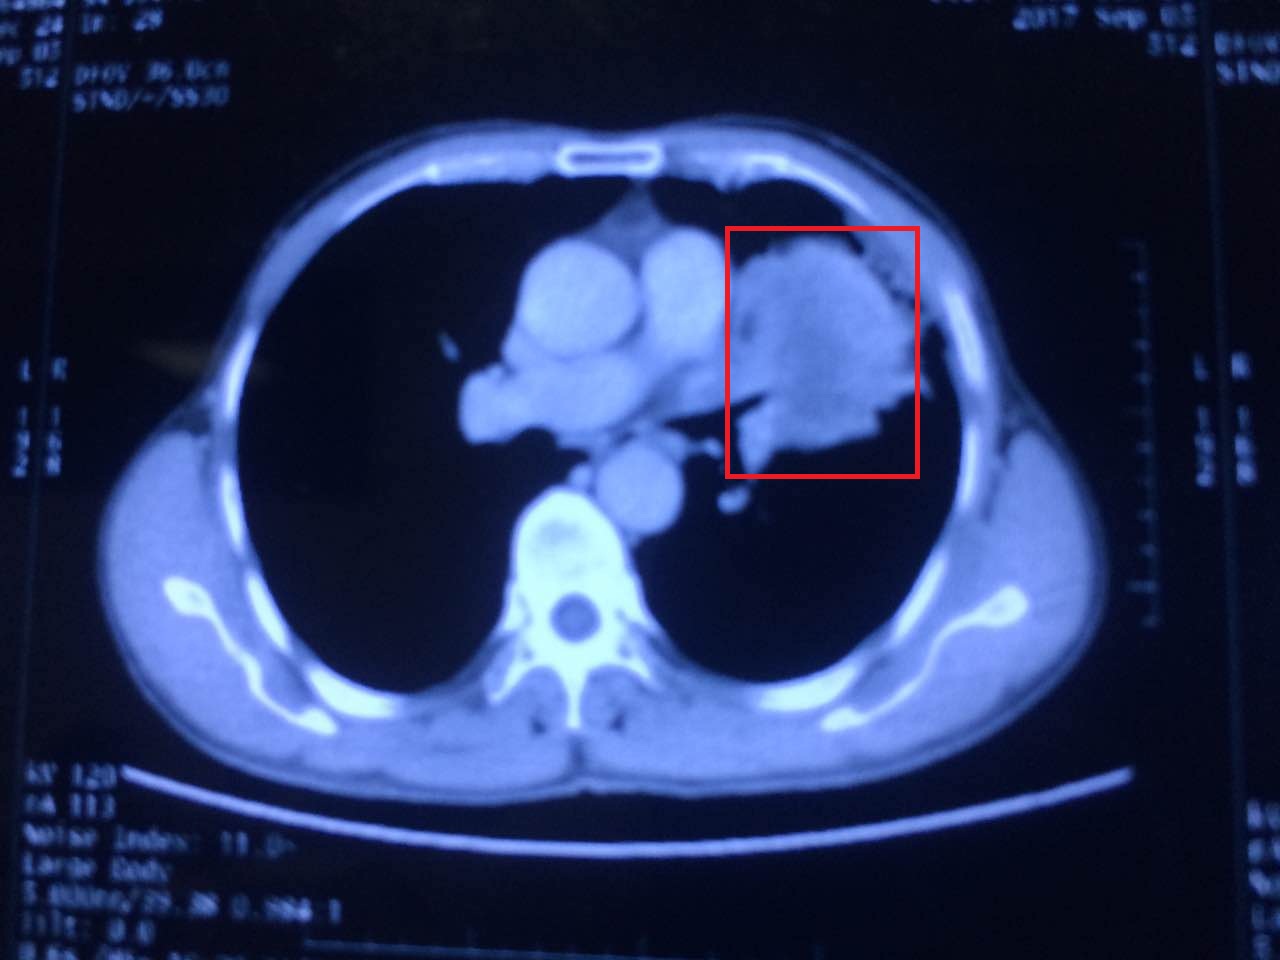

张伟教授仔细阅读了患者所带来的资料,发现为局部晚期肺部恶性肿瘤,未见远处转移,具备手术指征。但因包块巨大,手术难度大,且可能侵犯心包,手术风险极高。如若采取保守治疗,效果欠佳,病人生活质量得不到明显改善,手术切除仍是目前最佳选择。呼吸疾病中心医师团队结合患者实际情况,反复讨论研究,制定了缜密的手术方案及术中可能出现意外的应急方案。待术前检查完善后,于9月27日上午,张伟教授与科室团队一起开始了与病魔的战斗。

手术当中尽管遇到很多困难:致密广泛的肺部粘连、术中反复的低氧血症以及大量创面渗血,张伟教授及团队都一一应对自如。但当直视下看到肿瘤在肺门处侵犯的范围时,张教授纠结了:手术中肿瘤侵犯的范围远比术前胸部CT所显示的病变范围广泛。且病变已侵犯左肺动脉主干、左心房内,导致左上肺动静脉不能正常游离,离断。手术难度以及手术风险大家可想可知。虽然术前已经与患者家属做好了充分的沟通,手术策略也进行了周密的改动和详尽的安排。但目前最直接和残酷的选择摆在医生面前:放弃手术,患者则能平稳避开术中面临的巨大风险,顺利送出手术室。但患者远期受益明显降低,术后生存时间不长;继续手术,有极高大出血的风险,生命岌岌可危,但如果顺利切下肿瘤,患者远期生存时间将大大延长。这样的生死抉择,毫无疑问是对医生的技术和应对策略的极大考验。